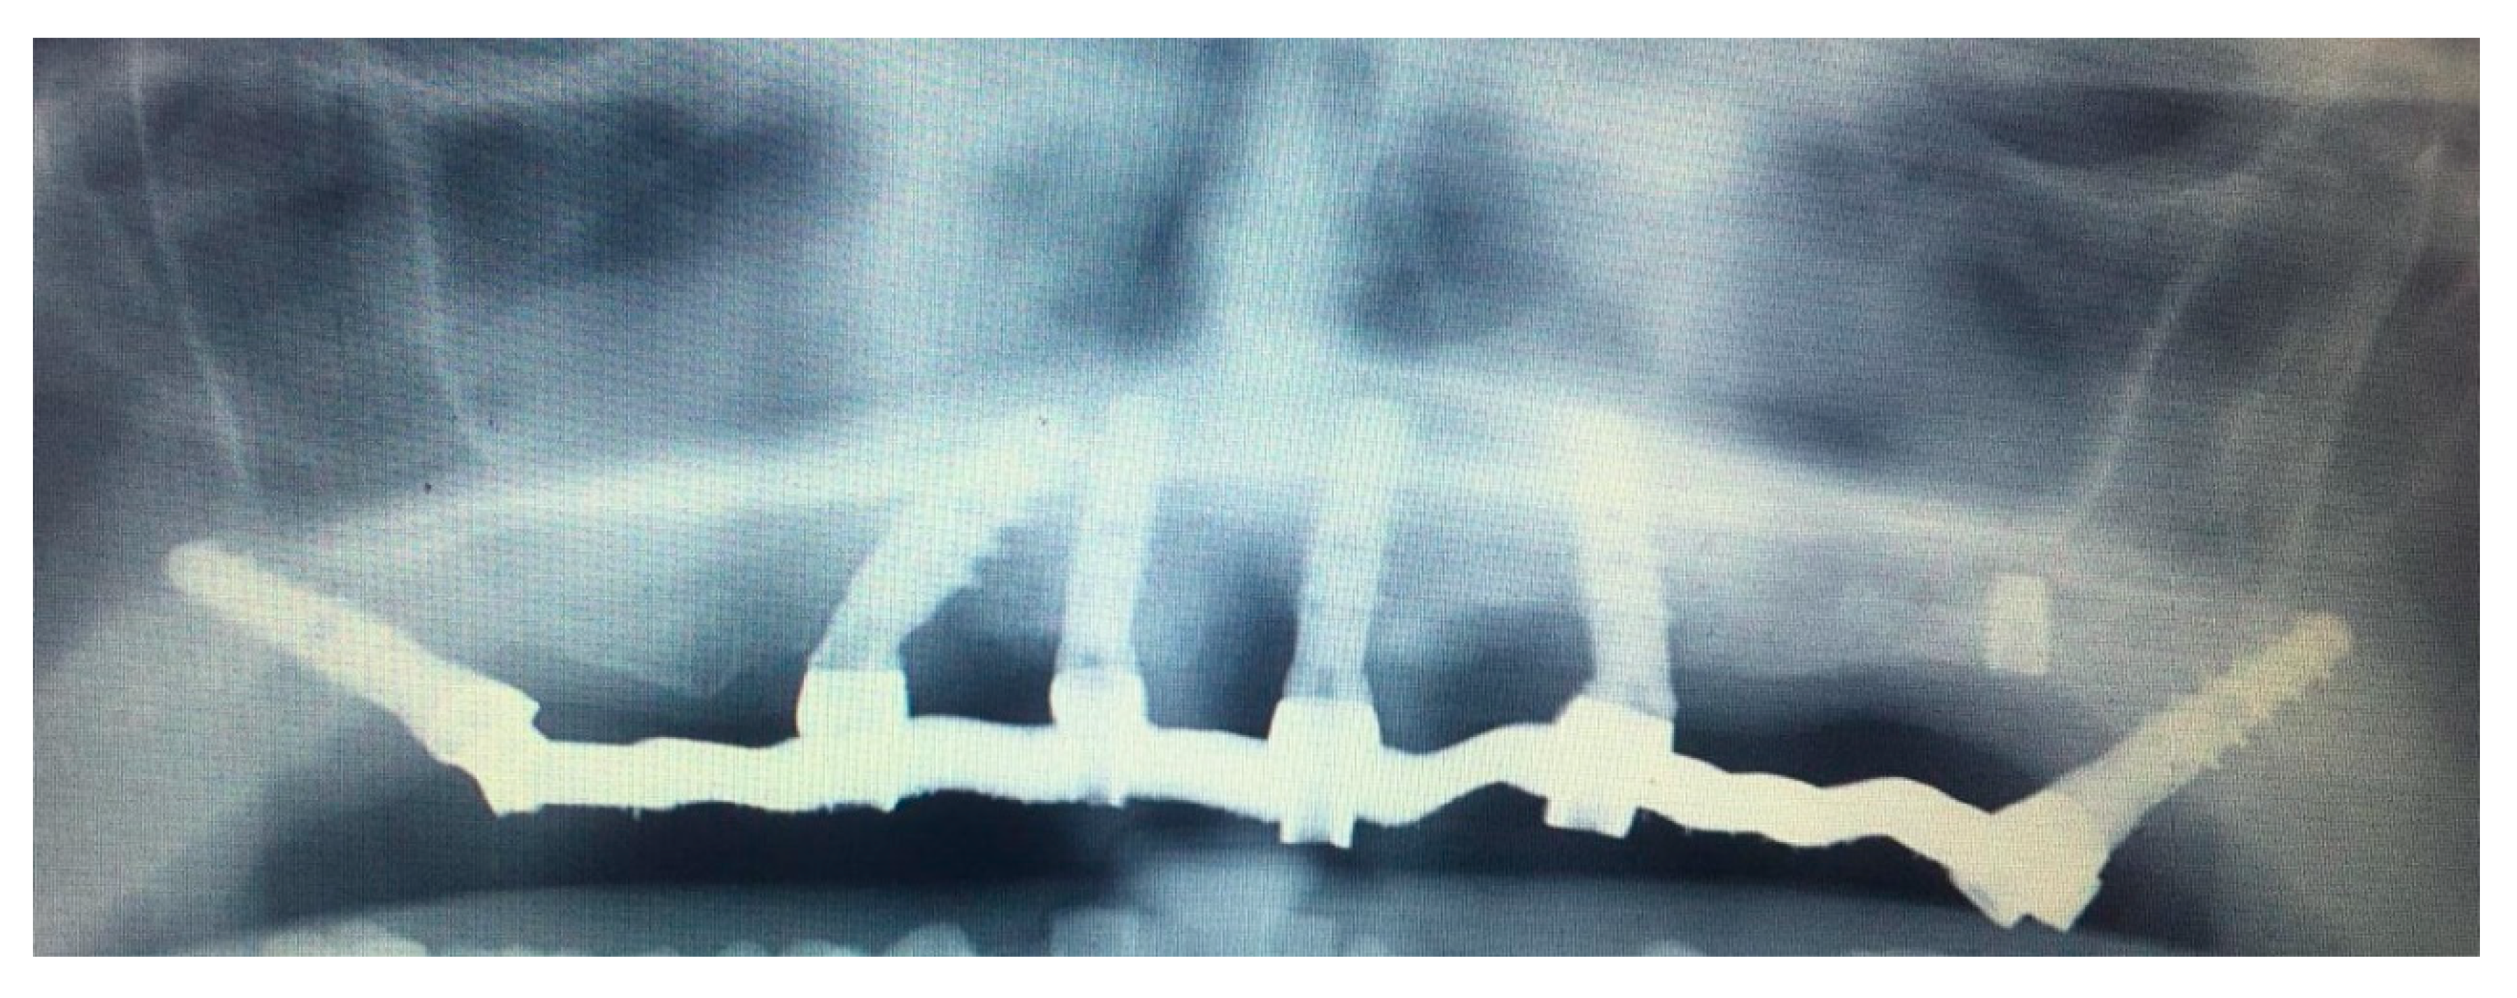

3.2. DCAI Approach Clinical Case